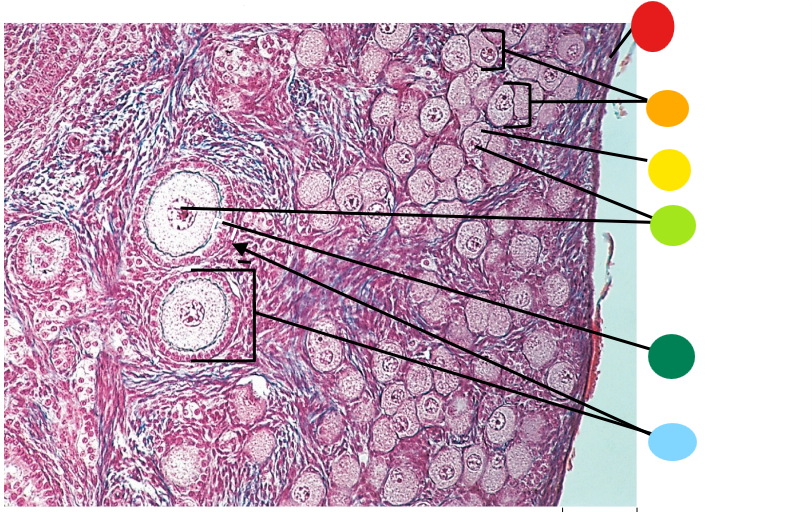

Lab H: Female reproductive histology

red

tunica albuginea

orange

primordial follicles

yellow

follicular cells

light green

primary oocyte

dark green

granulosa cells

light blue

primary follicles

what is this?

ovary